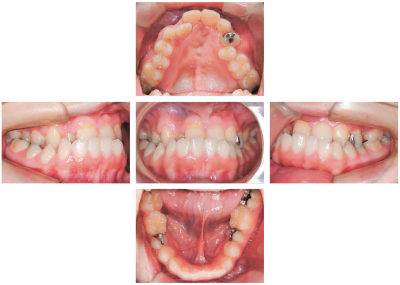

17 歳の女子。前歯部の反対咬合を主訴として来院した。これまで口唇口蓋裂の治療を受けている。診断の結果、外科的矯正治療を行うこととし、治療計画を立案した。初診時の顔面写真、口腔内写真、エックス線画像及び側面頭部エックス線規格写真を別に示す。セファロ分析の結果を図に示す。

動的治療終了後に使用するのはどれか。2つ選べ。